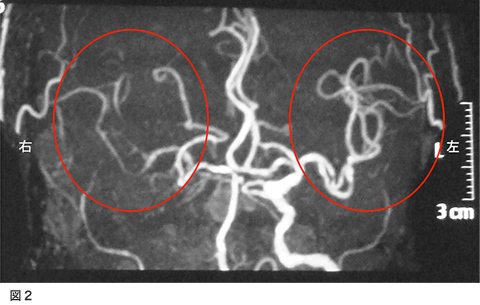

脳梗塞で発症された方です。意識障害と左不全片麻痺、構音障害で発症されました。図1が入院時のMRI拡散強調画像です。右側の白くなっているところが脳梗塞になっている部位です。図2の、MRA(MRIで行う血管の検査)では、右側の中大脳動脈の描出がほとんど無い状態でした。

4.術後MRA、脳血管造影

右は術後のMRAですが、術前ほとんど写っていなかった右中大脳動脈がバイパスからの血流で描出されるようになっています。左は、脳血管造影(右外頸動脈撮影)ですが、浅側頭動脈から中大脳動脈全域が描出されています。